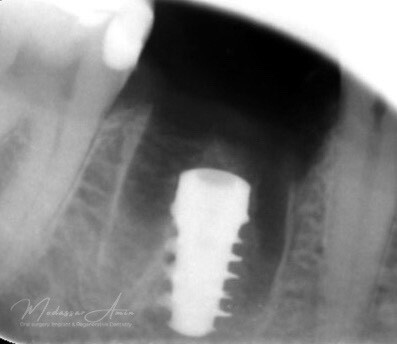

Kontrollröntgen för verifikation

Kontrollröntgen implantat